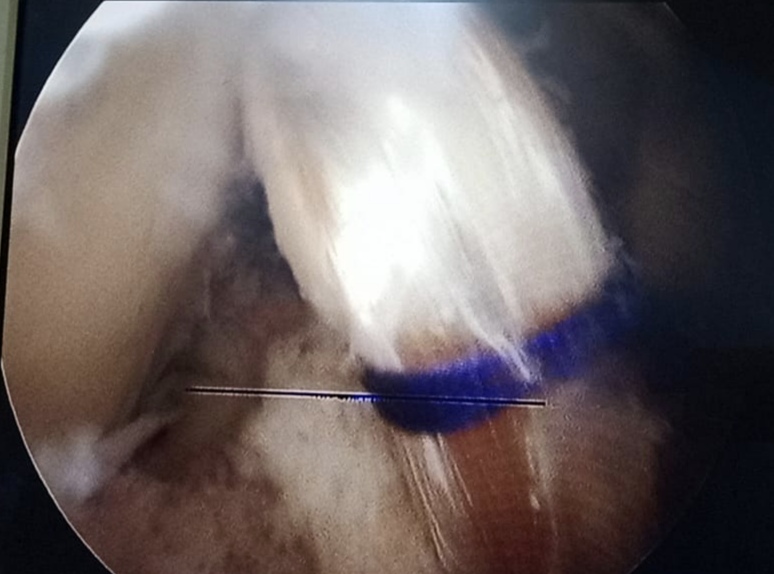

X-ray

Warning: Graphic Content

The following section contains graphic images of surgical procedures. These images are intended for educational purposes and may be disturbing to some viewers. Viewer discretion is advised.

Surgeries